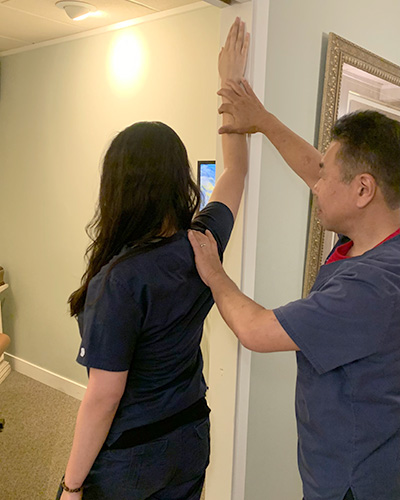

④ 自宅での運動

壁を使った簡単な運動で痛みを軽減できることもあります。肩関節の治療は根気と努力が必要不可欠。肩は日常生活で常に動きを伴い、睡眠時、仕事中、料理や掃除などの家事でも簡単にストレスがかかってしまい、休ませることの難しい関節です。当院では、ご自宅でできる運動もお教えしています。